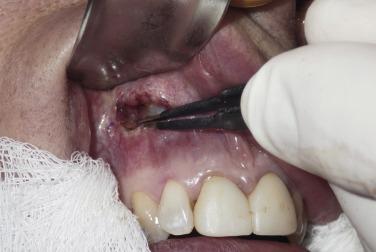

A 1-cm horizontal incision is made approximately 10–15 mm above the canine tooth. Using a radiowave or electrosurgery microneedle to incise the mucosa and soft tissues is hemostatic, and the incision is carried to the periosteal level of the canine fossa region ( Fig. 7.9 ). Alternatively, a vertical mucosal incision can be used but this approach provides less visual and working access compared with a horizontal entry. It is very common to see bleeding from the vascular rich mucosa and this is immediately cauterized with a small bipolar forceps to prevent bleeding throughout the case ( Fig. 7.10 ). The oral mucosa is very pliable, and even with a small incision, the surgical site can be well visualized when retracted. The incision continues to the periosteum and the entire dissection must remain subperiosteal. A Molt No.9 periosteal elevator is used to begin the subperiosteal dissection.